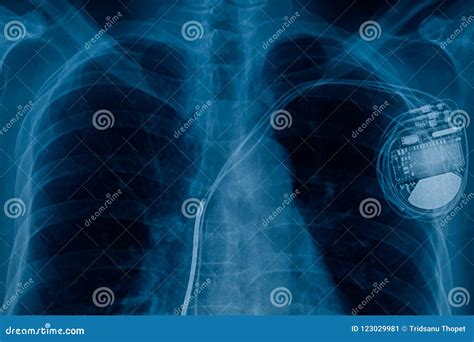

The study of cardiac pacemaker cells has significant clinical implications, particularly in the field of cardiology. Understanding the mechanisms by which these cells generate and propagate electrical impulses can lead to the development of more effective treatments for heart rhythm disorders. For instance, artificial pacemakers are devices that can be implanted to regulate the heart's rhythm in cases where the natural pacemaker cells are not functioning properly.

Artificial pacemakers work by delivering electrical impulses to the heart, mimicking the function of the SA node. These devices are programmed to maintain a specific heart rate, ensuring that the heart beats at a consistent and healthy rhythm. Modern pacemakers are highly advanced, with features such as rate responsiveness and dual-chamber pacing, which allow them to adapt to the body's changing needs and provide more natural heart rhythms.